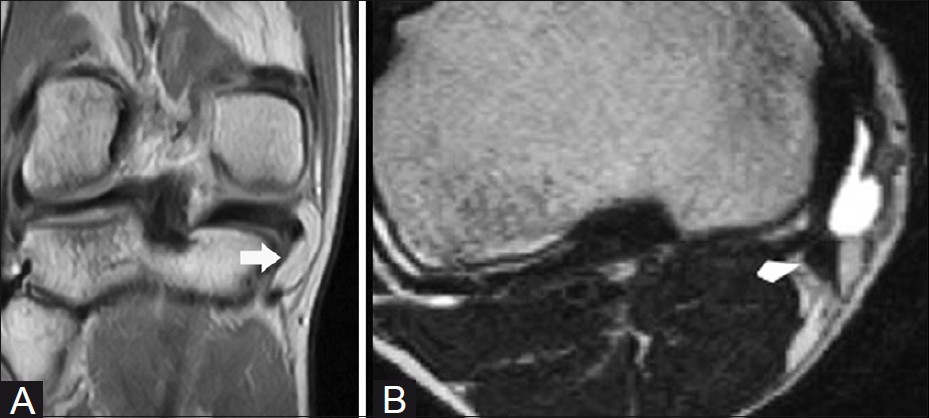

대부분의 정상적인 점액낭은 소량의 점액을 함유하여 MRI에서 잘 관찰되지 않지만, 염증성 변화에 의해 점액양이 증가되면 T1 영상에서 저신호 강도를, T2 영상에서 고신호 강도를 보이는 경계가 명확한 점액낭이 관찰된다.

△ 거위발 점액낭염(Pes anserine bursitis)의 MRI 소견

△ 내측측부인대 점액낭염(Medial collateral ligament bursitis)의 MRI 소견